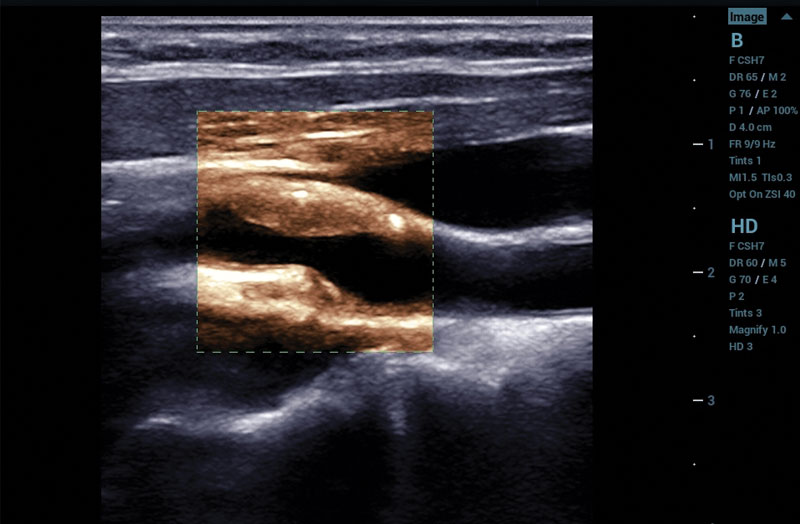

The ZS3 Ultrasound System Diamond Edition 2.0 is the ultimate imaging platform combining premium performance and mobility for today’s demanding ultrasound environments. Equipped with next generation ZONE Sonography® Technology+ (ZST+), the ZS3 System takes image clarity to new heights across a broad spectrum of body types from pediatric to bariatric. With every pixel in focus to imaging depths up to 40cm, the ZS3 System delivers unsurpassed image quality for the widest range of clinical applications.